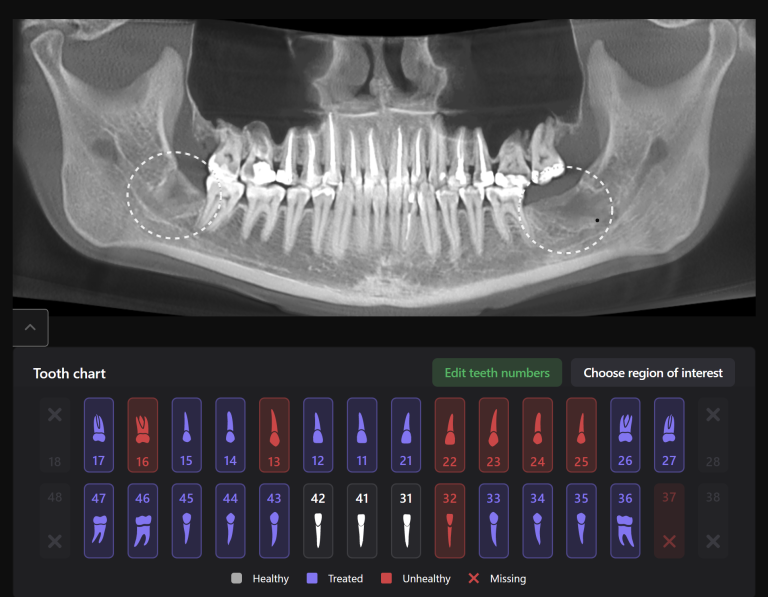

The second mesio-buccal (MB2) canal is notorious for being difficult to identify and is often left untreated, this can directly influence the outcome of the final treatment

Diagnocat AI helps us to see not only the consequences, but also the causes of the pathology. For example, in this clinical case – the missed MB2 during previous endodontic treatment of tooth 26 (Universal 14)

The 3D-Viewer allows the clinician to align the axes according to the area of interest and to study root canal morphology and anatomy before starting a treatment